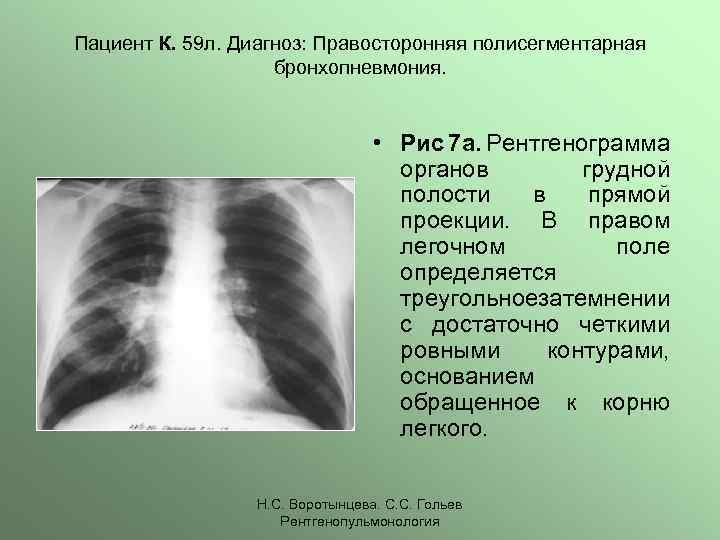

Рентгенодиагностика бронхопневмонии: Советы и примеры

Раздел: Альбом открытий